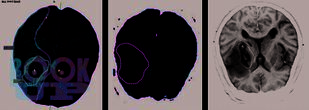

Диагностика острого нарушения мозгового кровообращения совершенствуется в соответствии с прогрессивным развитием лучевых технологий диагностики, что требует определенного обновления информационных материалов с большей детализацией трактовки получаемых данных. Качественно и оперативно полученные сведения становятся основой для клинического решения при выборе методов специализированной помощи. Современный Порядок оказания помощи больным с ОНМК требует раннего определения причинно-следственных связей развития острой цереброваскулярной катастрофы и проведения динамической оценки патогенетических процессов повреждения вещества головного мозга, что возможно только при условии тесного взаимодействия нейрорадиологов и неврологов.

В монографии изложены наиболее полно изученные, наименее спорные и широко применяемые в современной рутинной практике клинико-инструментальные диагностические закономерности, отражающие патогенетическую последовательность и гетерогенный характер острого цереброваскулярного повреждения головного мозга. Предложены типовые диагностические алгоритмы, применяемые в остром периоде заболевания.